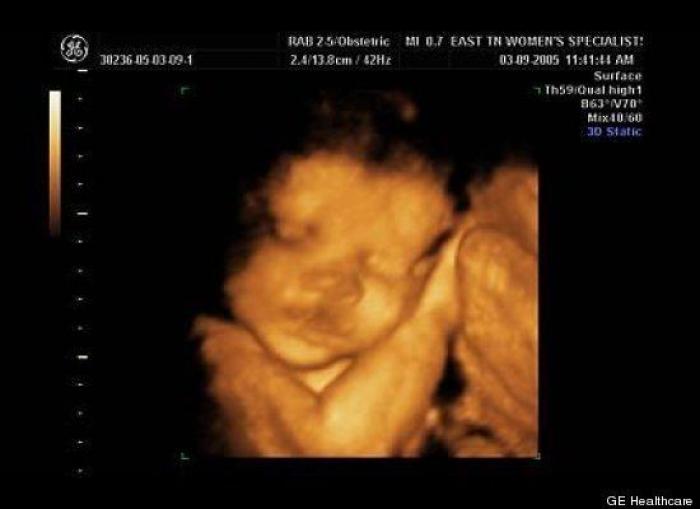

En esta galería puedes ver en fotos como es el desarrollo de un feto de semana en semana:

Desarrollo del feto, en fotos